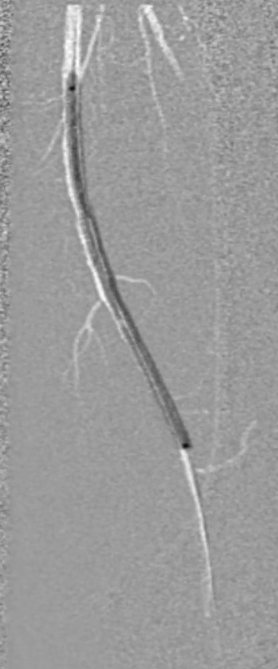

操作要点:在路径图引导下,使用超滑导丝配合6F导管选择进入支架近端(避免导丝从支架网眼穿出),随后采用新型超声开通导管尝试开通病变段。

器械优势:超声导管头端可发射超声波,能轻松通过坚硬闭塞部分;

注意事项:该导管硬度较大、方向选择性差,需配合V18导丝引导,推进时需缓慢操作并密切关注患者疼痛等不良反应。

调整与确认:开通至股浅动脉中段后,发现导丝向另一个方向打弯,退回后重新选择路径,最终顺利送至股浅动脉远端真腔,造影证实开通成功。